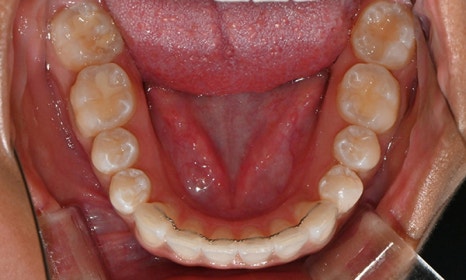

위아래 앞니 사이가 벌어져서 공간이 있었고, 앞니에 약간씩 배열이 틀어진 덧니가 있었습니다. 정면에서 보았을 때 윗니와 아래 앞니가 깊게 물려서 아래 앞니가 잘 보이지 않는 과개교합 양상을 보이고 있었습니다. 또한 왼쪽 아래 작은 어금니가 90도 앞으로 돌아가서 좌측 치아 배열 및 교합이 좋지 않은 상태였습니다.

초진시 구내사진 (2025. 3.31)